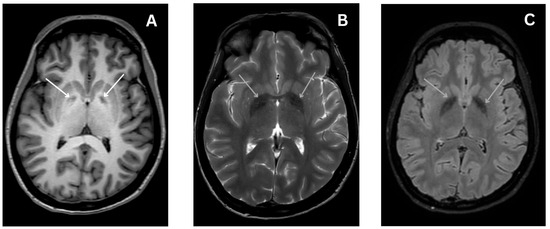

Early Diagnosis of Central Disorders Mimicking Horizontal Canal Cupulolithiasis

Background: Horizontal Canal Cupulolithiasis (hc-BPPV-cu) can mimic a pathology of central origin, so a careful examination is essential to prevent misdiagnosis. Methods: Retrospective cross-sectional cohort study of 45 patients suffering from suspec...